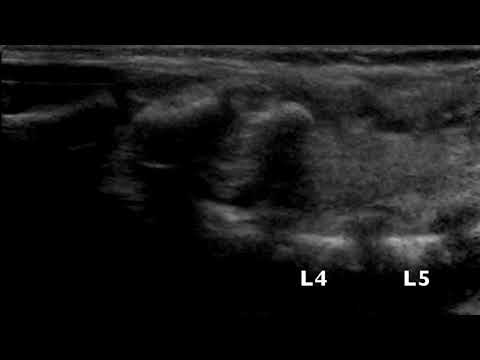

Spinal US - conus at L5